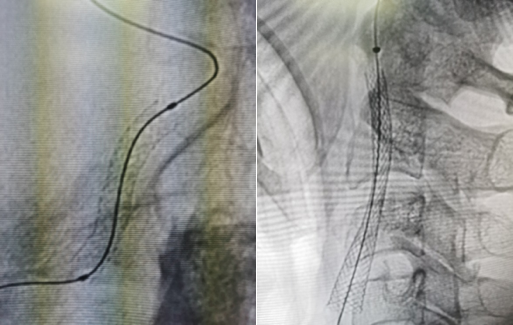

图10 由远及近依次使用2.0 mm的球囊扩张

图11 扩张后见正向血流出现,但管腔情况不理想

图12 使用4mm球囊再次扩张全段血管,此时正向血流已明显改善,但发现C1及岩骨段-海绵窦段交界处存在狭窄,再次扩张后狭窄改善不理想

图13 于海绵窦段-岩骨段交界处植入球扩支架一枚,展开过程球囊充盈受限明显,颈内动脉开口处植入自膨支架一枚

图14 造影可见颈内动脉血流稳定